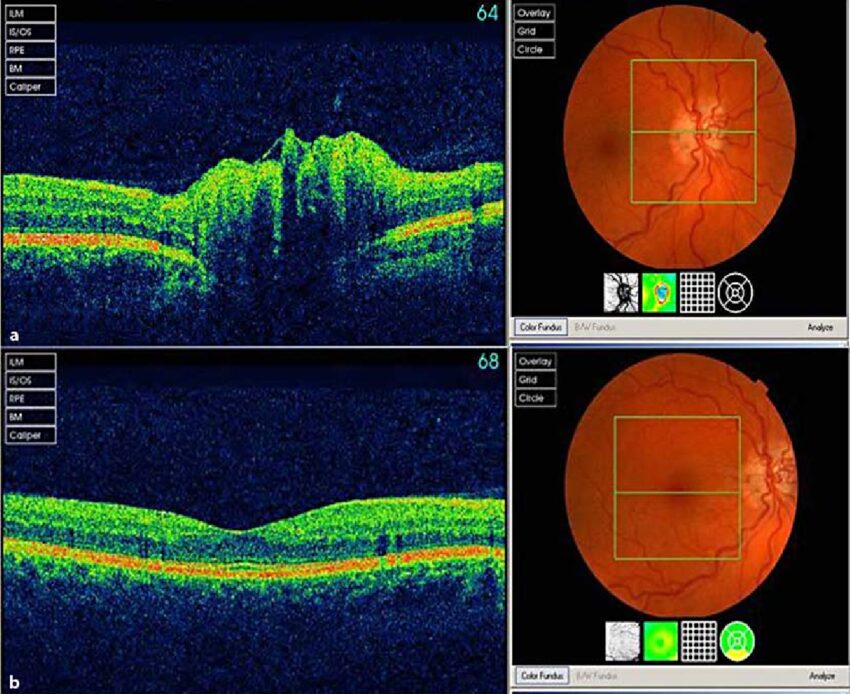

• Retinopatia Diabetică: OCT este esențială în diagnosticarea și monitorizarea acestei afecțiuni comune la persoanele cu diabet.

• Degenerescența Maculară legată de Vârstă: OCT este folosit pentru a monitoriza această afecțiune progresivă care afectează macula.

• Gaura Maculară: OCT poate identifica această afecțiune care afectează centrul retinei.

• Edemul Macular: OCT este folosit pentru a detecta acumularea de lichid în maculă.